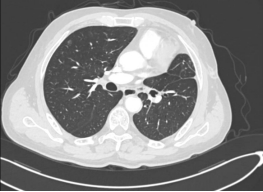

患者1为73岁男性,确诊中央型肺鳞癌(肿块大小约3.8cm),此前因化疗后出现消化道出血,无法耐受传统治疗方案。杨超教授团队创新性采用“介入灌注化疗+微创手术”联合方案,先通过介入治疗降低化疗副作用,再行左下肺癌根治术+左上肺支气管袖状切除术,成功为患者保留健康肺组织。术后病理检查证实切缘无癌残留,患者恢复良好,家属由衷感慨:“多家大医院建议全肺切除,没想到在这里保住了肺!”